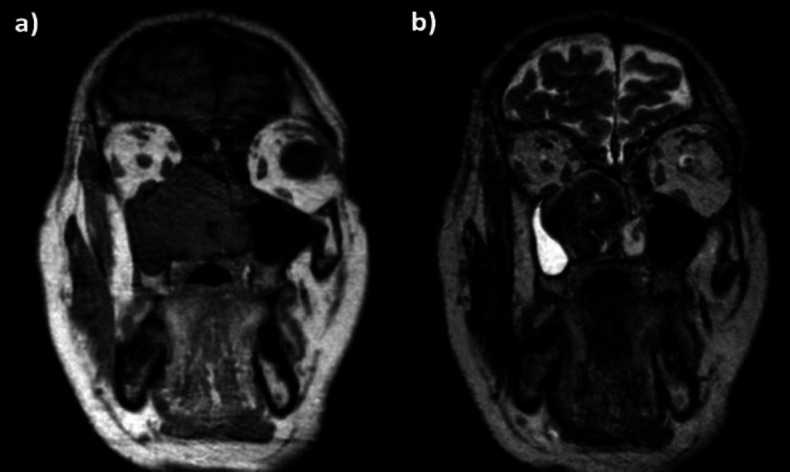

Case report: This case report shows a rare right nasal septal solitary fibrous tumor, which was surgically removed using a trans-nasal endoscopic technique. For the first time, the mass was decomposed by a plasma blade, and the implant site was treated by performing a subperiosteal removal of septal mucosa and cartilage. Histopathological examination confirmed the diagnosis of solitary fibrous tumor. Follow-up at three, six, and twelve months showed no signs of relapse.